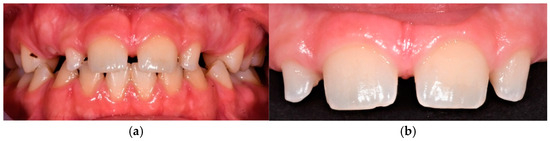

2.1.5. Therapeutic Intervention

2.2. Case 2

2.2.5. Therapeutic Intervention